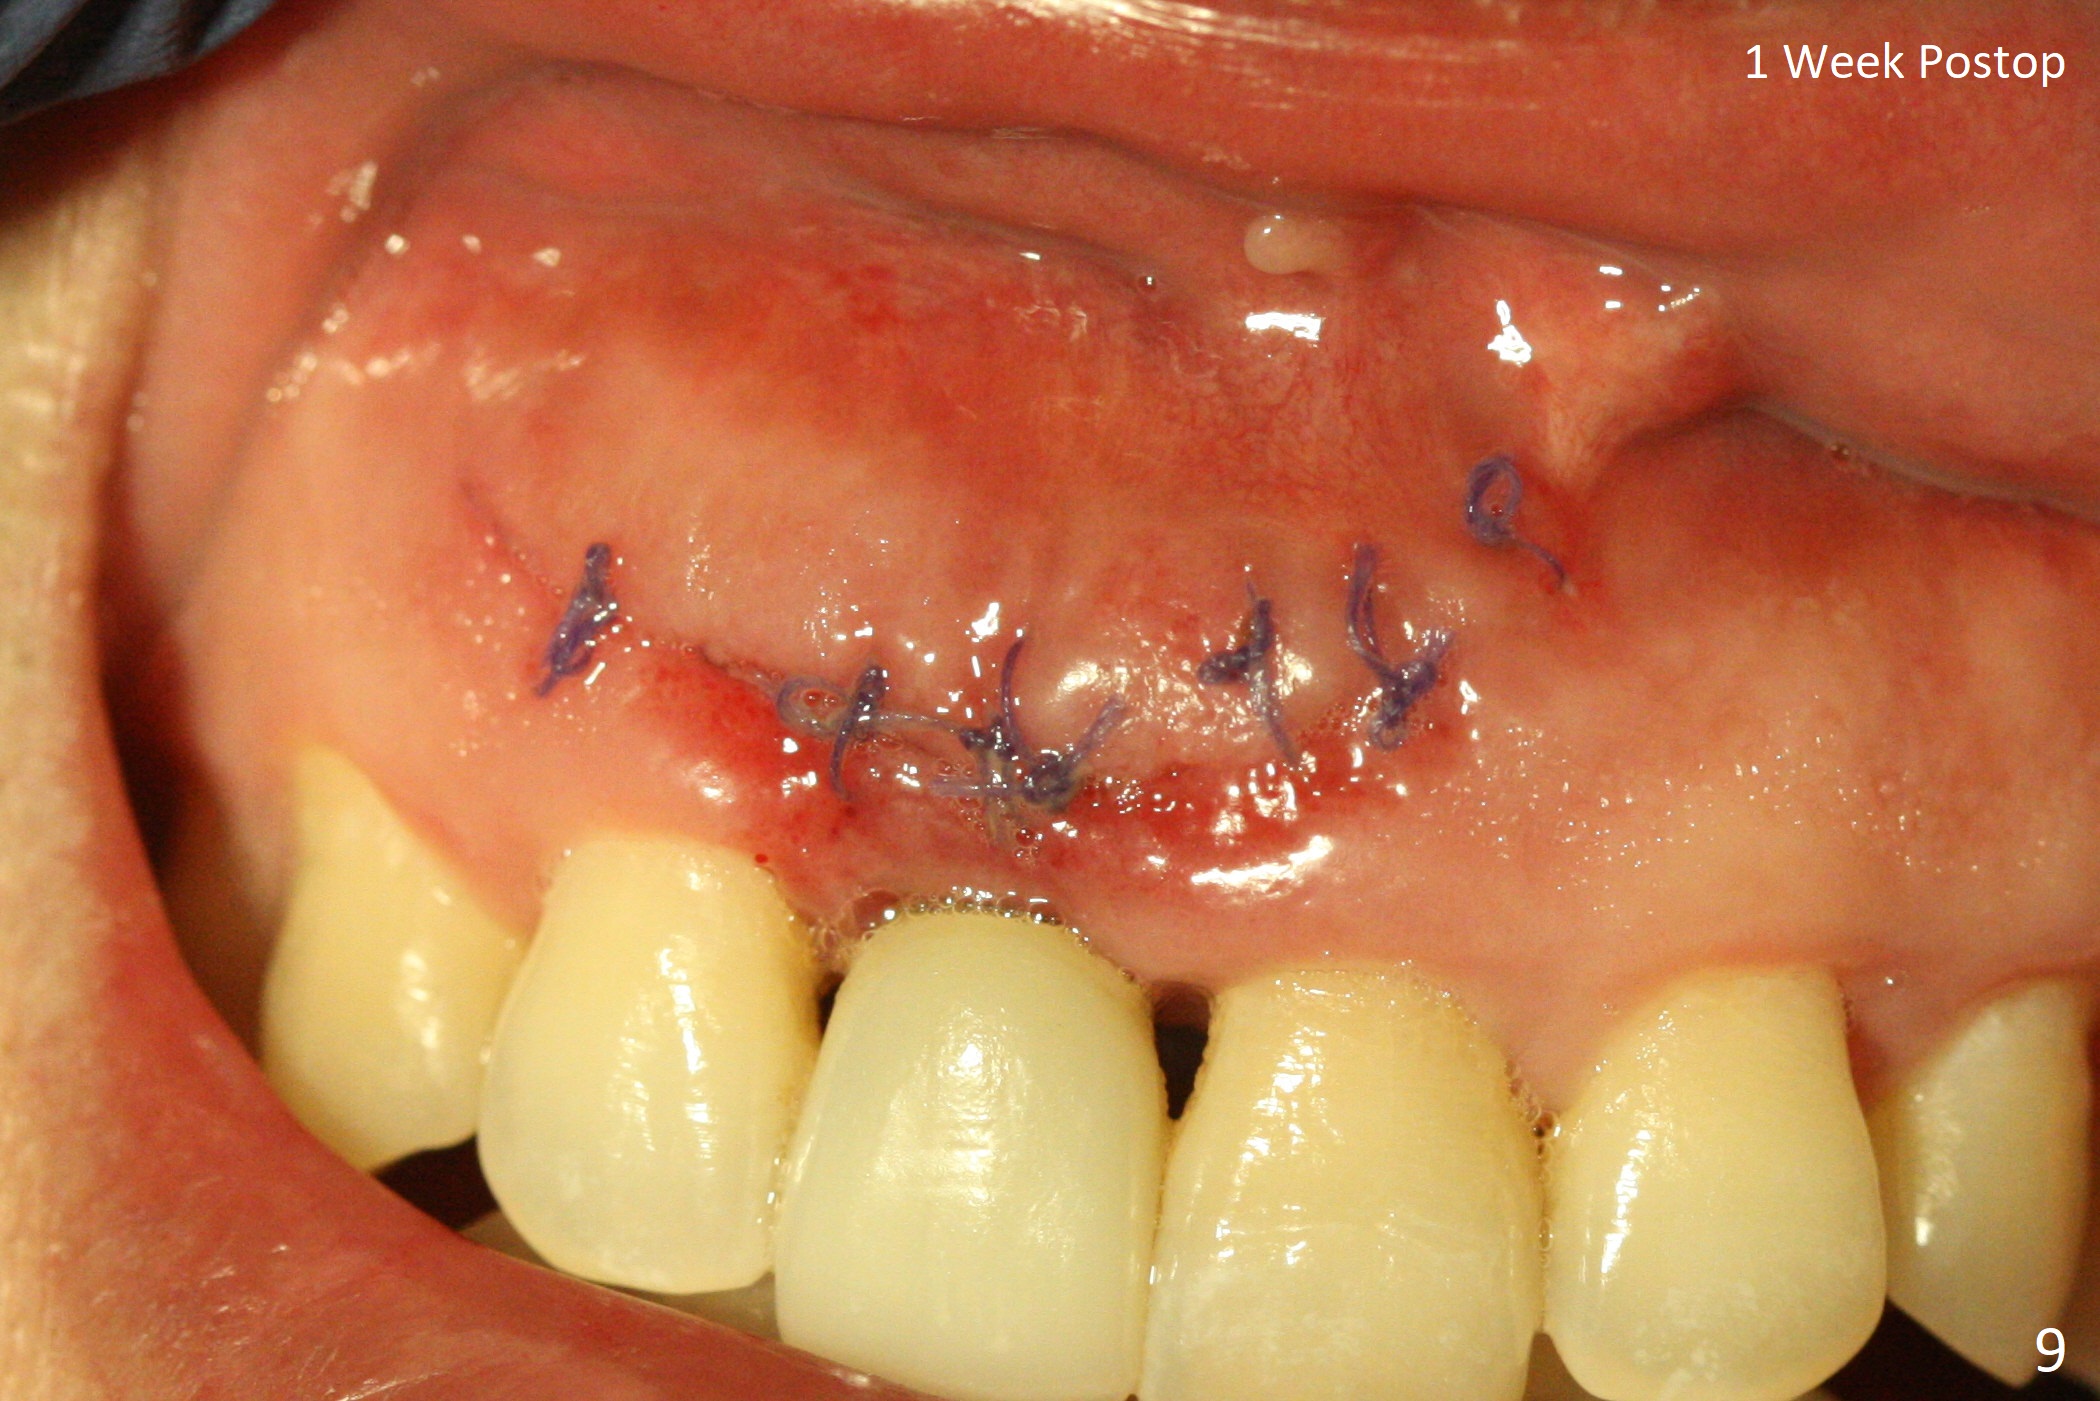

The patient returns because of purulent exudate from the buccal fistula (Fig.1 *) 1 year 9 months postop (1 year 3 months post cementation). Preop CT shows buccal thread exposure (Fig.2 arrowheads). To prevent postop gingival recession, a semilunar incision is made between the fistula and the gingival margin (Fig.3). After removal of granulation tissue (Fig.4), allograft in sticky bone form is packed (Fig.5). Following placement of PRF membrane and 6-month collagen membrane, the wound is closed (Fig.6). Since the implant (Fig.7 I) thread exposure is within bone (B) boundary (Fig.8 red dashed line), bone graft with PRF should be able to take care of periimplantitis (A: abutment). To prevent periimplantitis in similar situation, the immediate implant should be placed deep (not necessarily long, 18 mm) and narrower (3.5 mm instead of 3.8 mm). The defective buccal plate should be repaired with sticky bone and collagen membrane with incision if necessary. The wound does not dehisce 1 week postop (Fig.9) or 3 weeks postop (Fig.10, immediately post suture removal). Although bone graft seems to stay in place 6 months postop (Fig.11,12), the patient complains of bone graft expulsion sometimes. The buccal gingiva has deficiency (Fig.13). To fix it, make a remote incision (Fig.14 black line) and dissect before gingiva graft (Fig.15 dashed line). After removal of crown/abutment, the sinus track and implant surface are treated with Waterlase. A shorter cuff abutment is placed (4.5x5(4 to 3) mm) with a new provisional. The patient feels better with reduced sinus track 2 weeks postop (Fig.16).